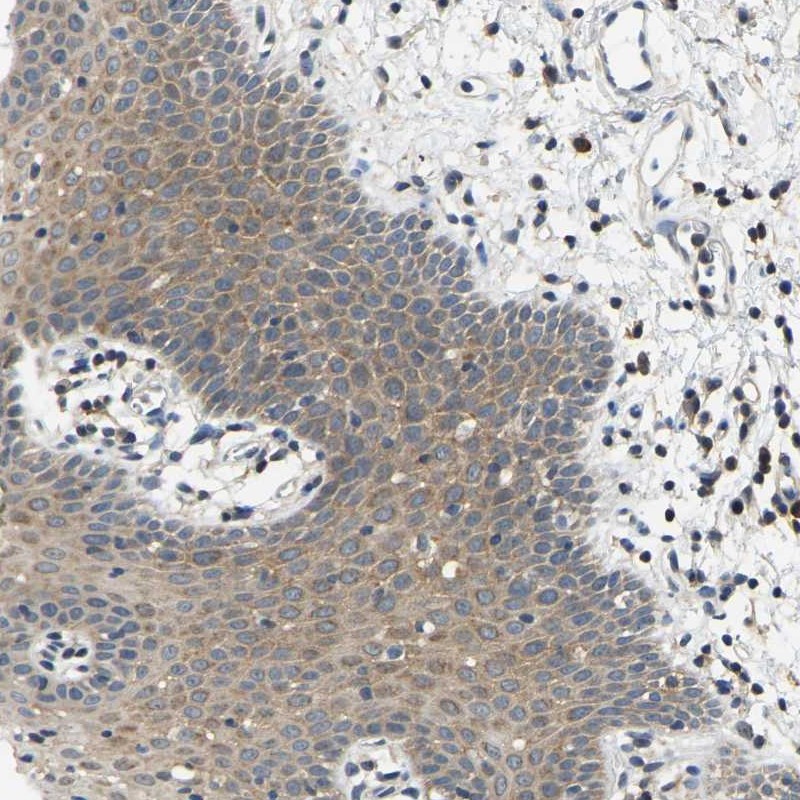

Immunohistochemical staining of human oral mucosa shows cytoplasmic positivity in squamous epithelial cells.